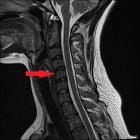

Причины развития, симптомы и лечение нарушения мозгового кровообращения при шейном остеохондрозе. Как лечить сосудистые нарушения при остеохондрозе..